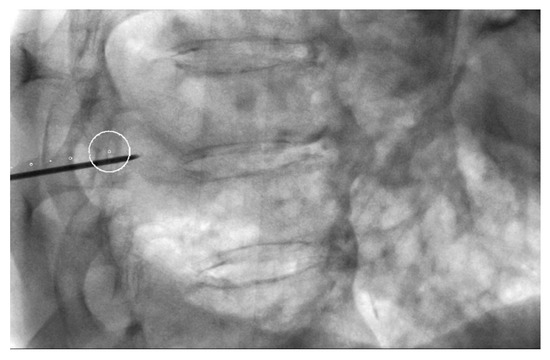

Cone-Beam CT-Guided Lung Biopsies: Results in 94 Patients

- Cone-Beam CT-guided biopsy is a highly accurate and safe technique with a sensitivity of 91.5% and a specificity of 100%.

- Risk factors for pneumothorax are a deeper location of the nodule and prone position of the patient in the procedure.